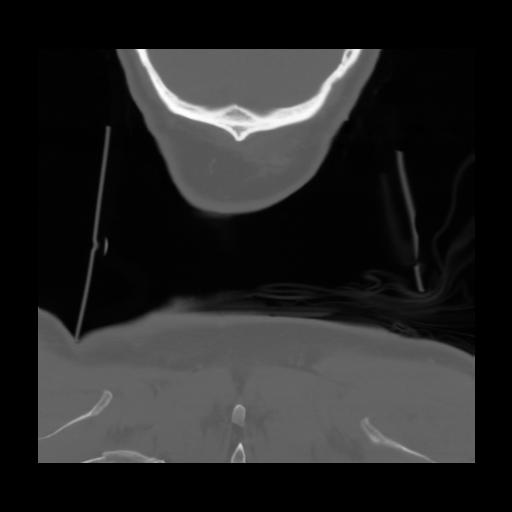

13 P.BLANDAS,,Coronal,2.000,P.BLANDAS,Coronal,